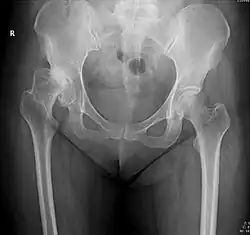

La subluxation de la hanche est la perte de contact, partielle et permanente, entre les deux surfaces articulaires que sont la tête fémorale et le cotyle.

Dans le langage médical, une luxation désigne un déplacement d'une surface articulaire par rapport à une autre. Il y a alors une rupture de continuité articulaire, comme si l'articulation se déboitait. Dans le cas d'une subluxation, la perte de contact n'est pas totale. Très douloureuse, la subluxation acquise de la hanche occasionne une impotence partielle voir complète du membre touché soit des difficultés voire une impossibilité à se servir de l'articulation de la hanche.

La subluxation est principalement la conséquence d'une malformation de la hanche congénitale dite dysplasie de la hanche ou de façon plus moderne dysplasie développementale de la hanche[1]. Elle est plus rarement la séquelle d'une luxation mal traitée. Elle peut aussi être la conséquence évolutive d'une infirmité motrice cérébrale avec tétraplégie[2].